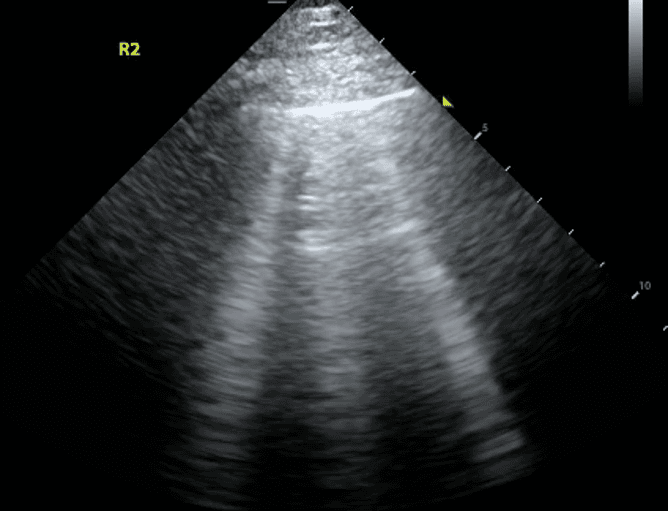

Recall that B lines are vertical hyperechoic artifacts originating from the pleural line that look similar to comet-tails.

B lines reflect interstitial syndrome and the number of B lines increase with decreasing air content in lungs and thus, increasing lung density. To narrow down this broad differential, one can evaluate whether the B lines are present in a diffuse or focal (clumped together) pattern, look at abnormal pleural line patterns and look for other features of abnormal lung on ultrasound.